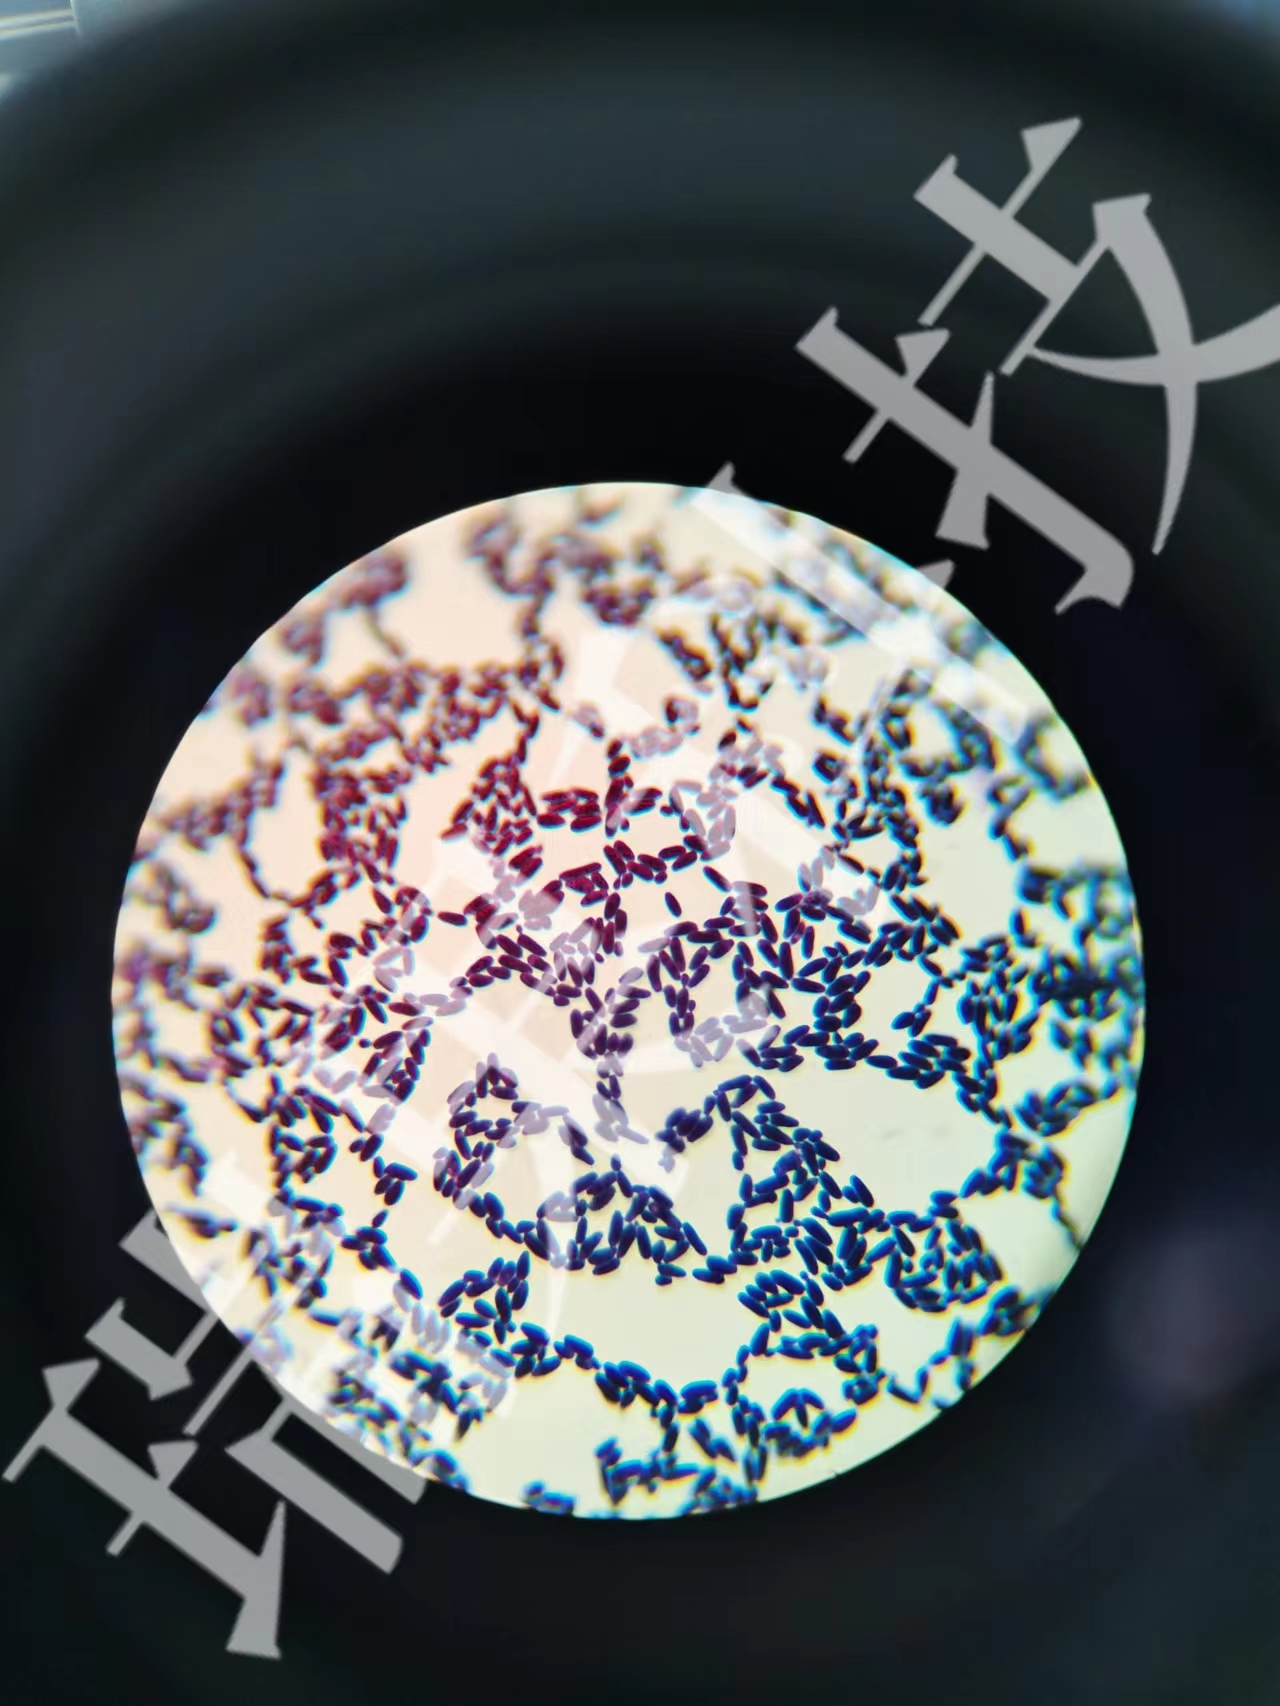

IL-1主要由巨噬细胞、单核细胞、树突状细胞等先天免疫细胞分泌。当这些细胞感受到来自细菌、病毒、或组织损伤释放的危险信号(如病原体相关分子模式PAMPs或损伤相关分子模式DAMPs)时,IL-1的合成和释放就会被迅速触发。